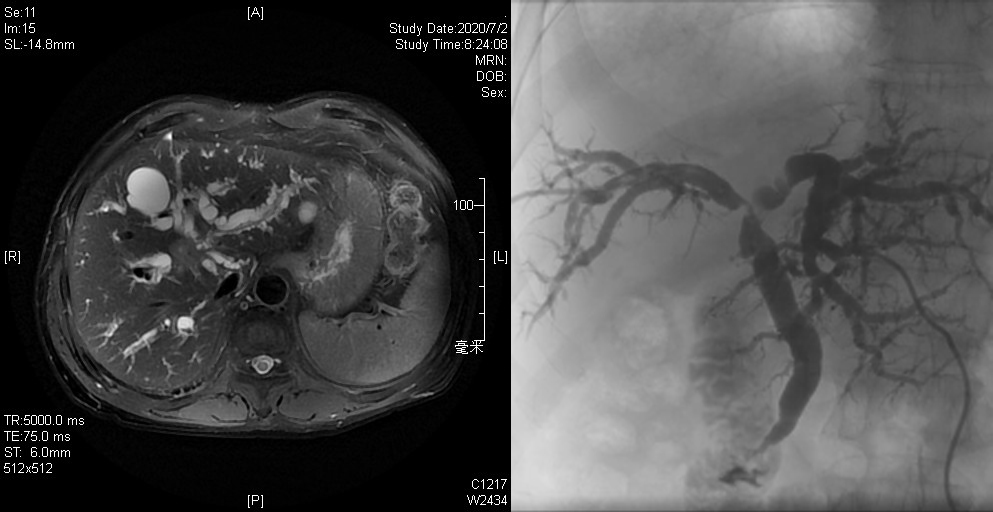

术前MRI显示肿瘤及肝内胆管扩张(左)      PTBD显示肝门区胆管侵犯、狭窄(右)